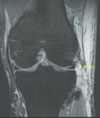

7

Q

Knee: Osteochondritis dissecans

PE and test

A

Physical Exam:

Localize joint line tenderness

Occasionally will have effusion

Occasionally will have popping

Tests: start with X-Rays (knee – notch view) but MRI is needed to determine severity

8

Tx and pearls

Treatment:

Kids: more conservative tx like rest, cast, NWB x several months

Adults: stable – weight bearing restrictions, unstable surgical repair – drilling, screw fixation, resurfacing, joint replacement

Both require surgical removal if there is a loose body in the joint

Pearls:

Most common location of OCD in the knee is the posterior lateral aspect of the medial femoral condyle (70%), capitellum of humerus, talus